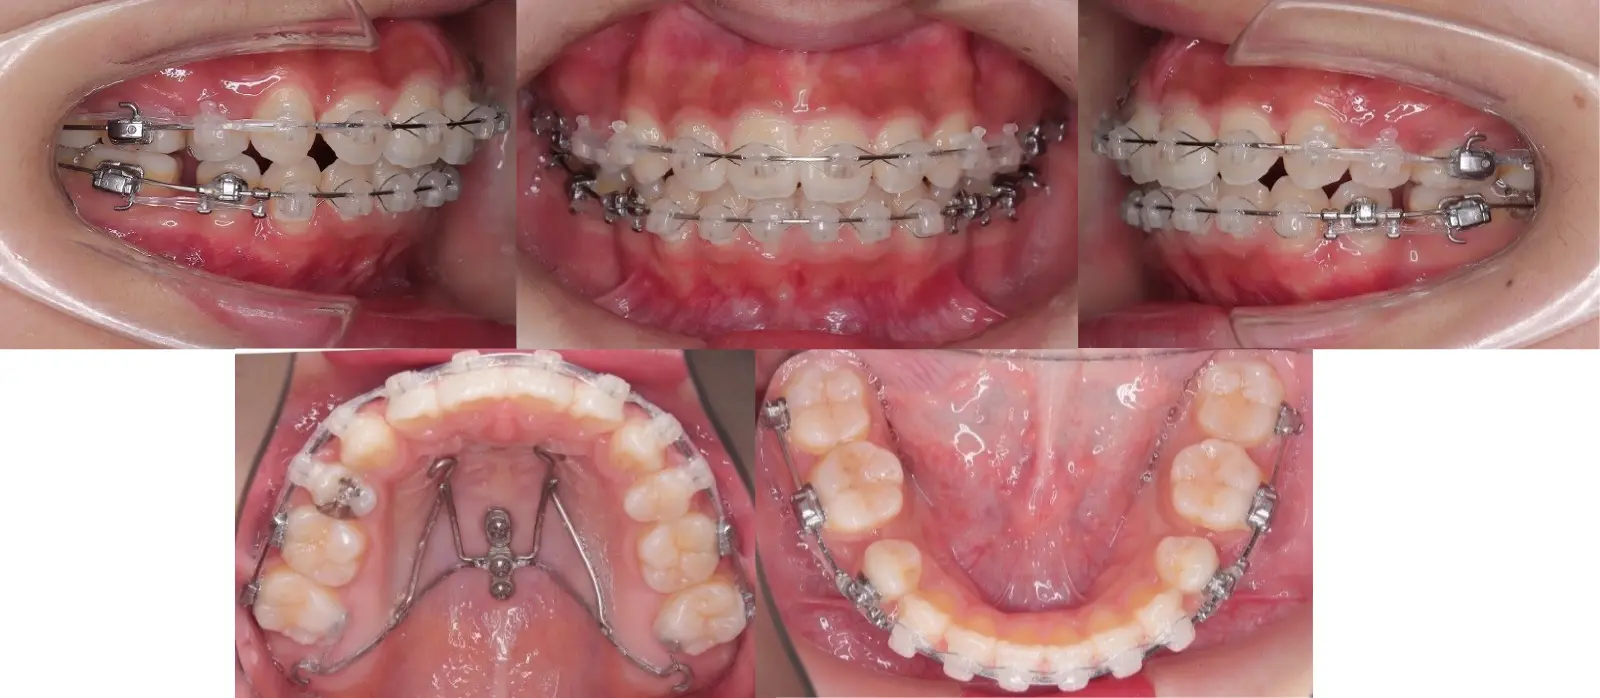

アングル1級叢生と過蓋咬合を伴う上顎前突症

- 主訴

口元の突出感と乱食歯

- 年齢

10代

- 治療期間

1年5ヶ月

- 治療回数

16回

- 治療に用いた主な装置

カスタムメイド型マルチブラケットタイプのデジタル矯正装置(インシグニア)

- 治療費

630,000円(税別)、調整料5,000円(税別)

- 抜歯部位

上下顎第一小臼歯 計4本